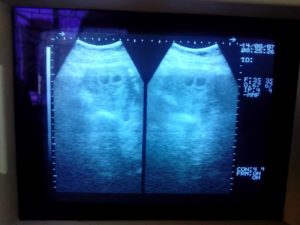

Pas di USG agak kaget juga ngeliat hasil USG nya.

Ternyata disini langsung ketauan, ada 2 kantong kehamilan disana. Ditanyain sama dokternya apakah ada riwayat keturunan kembar, soalnya kemungkinan besar ini janinnya kembar. Kaget dan shock banget itu yang dirasain saat denger penjelasan dokternya. Apalagi dari keluarga bunbun dan keluarga mas Soleh juga ga pernah ada riwayat keturunan kembar. Trus dokternya juga sempet ngejelasin tunggu sampai 2 minggu lagi. Kalo janin nya tumbuh semua di 2 kantong kehamilan tersebut, maka positif bayinya kembar. Tapi bisa juga terjadi hanya satu janin yang tumbuh, dan janin yang satunya lagi melebur dan terjadilah kehamilan tunggal. Atau bisa juga terjadi BO (Blighted Ovum)Â yaitu ga ada janin yang tumbuh satupun yang artinya ga ada kehamilan yang terjadi alias gugur dan itu harus di kuret.

Dan ini lah hasil USG mereka